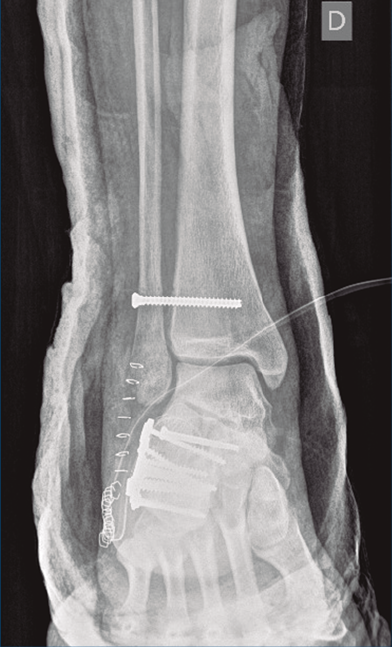

Figura 9. Control radiográfico posquirúrgico, anteroposterior.

Figura 10. Control radiográfico posquirúrgico, lateral.

Se dio de alta el día siguiente a la cirugía con un buen control analgésico. En la radiografía de control postoperatoria presentó una correcta reducción tanto de la fractura de calcáneo como de la articulación tibioperoneo astragalina (Figuras 9 y 10). Se citó en consultas externas 2 semanas después para la retirada de la sutura, presentado un buen aspecto las heridas quirúrgicas (Figura 11), y para la colocación de un botín de yeso. Dicho botín fue retirado al mes y medio de la cirugía, colocándose una ortesis estabilizadora de tipo Walker y autorizándose la carga parcial y progresiva, comenzando la rehabilitación.